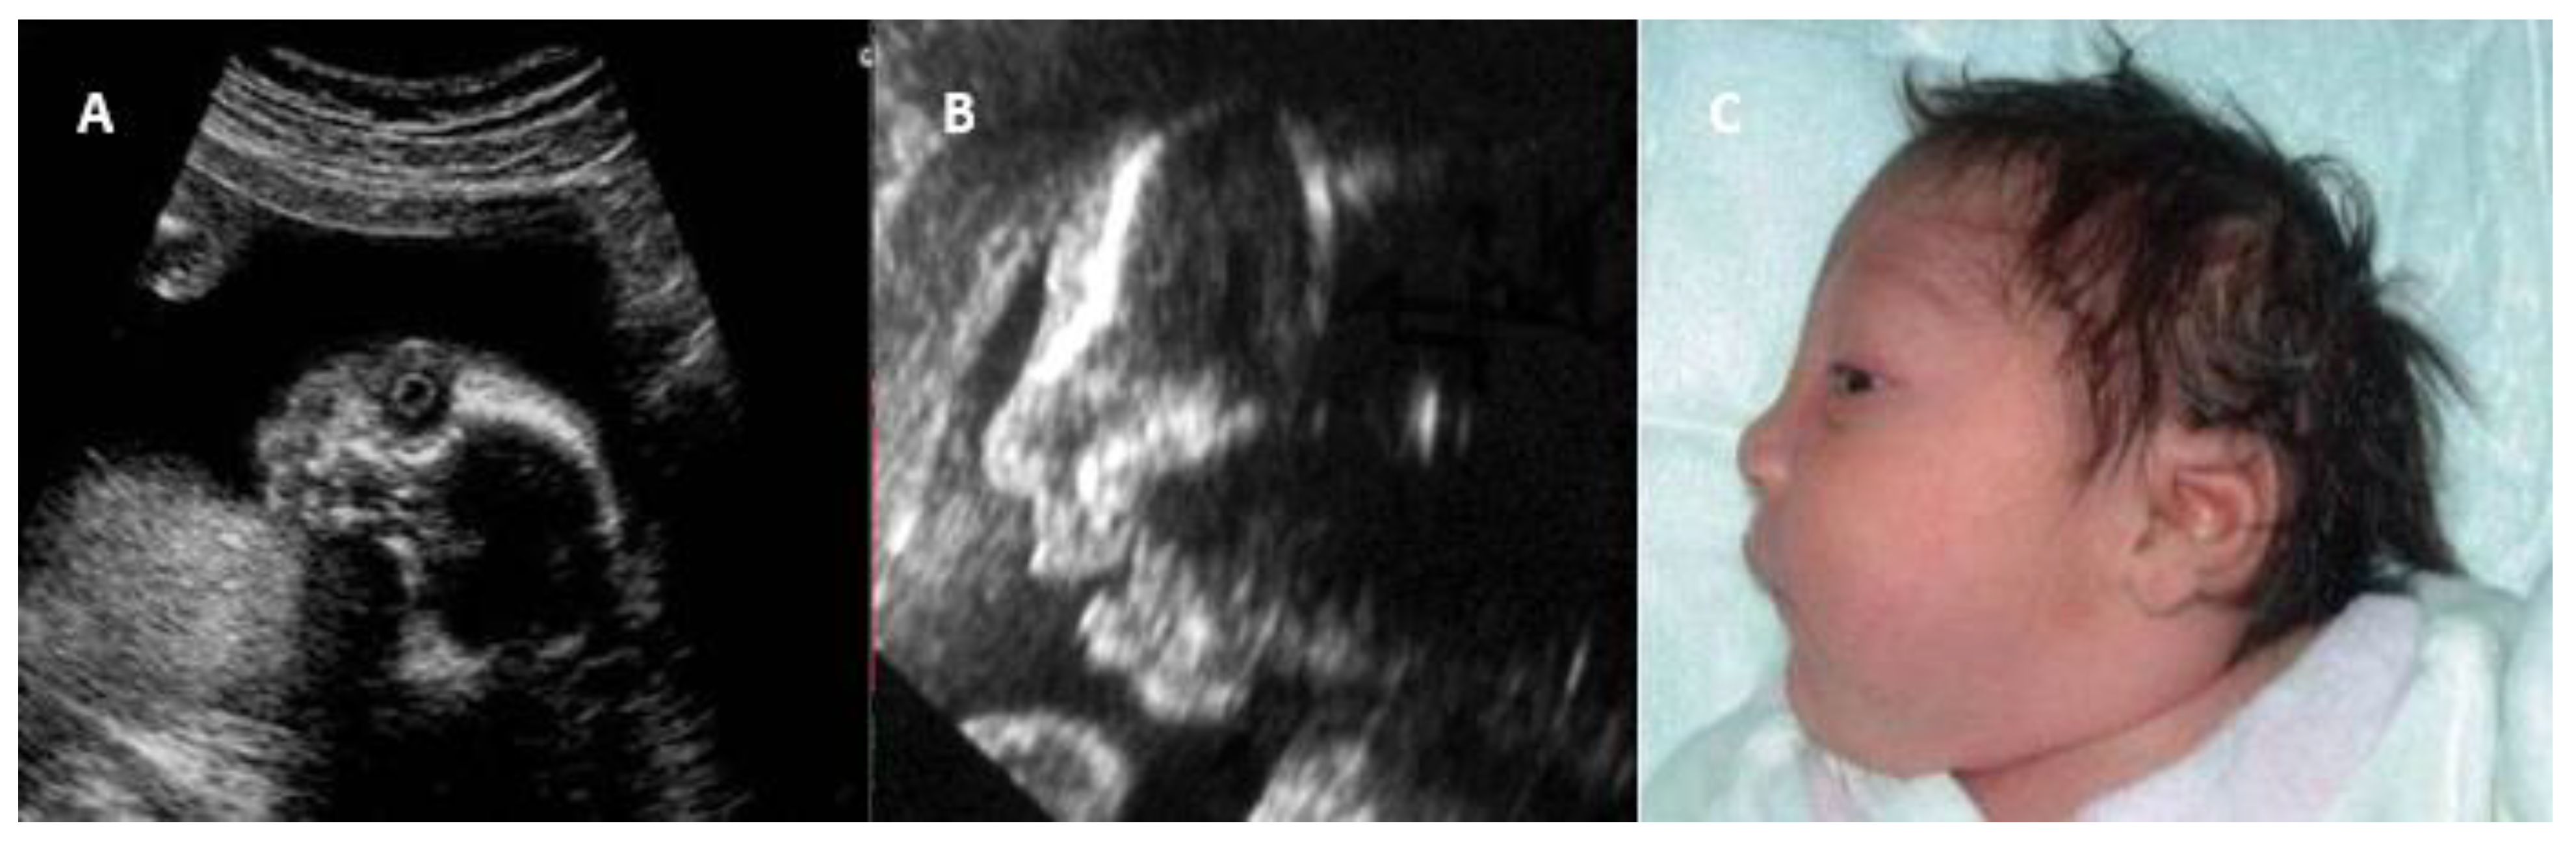

- Migliucci, A.; Di Fraja, D.; Sarno, L.; Acampora, E.; Mazzarelli, L.L.; Quaglia, F.; Mallia Milanes, G.; Buffolano, W.; Napolitano, R.; Simioli, S.; et al. Prenatal diagnosis of congenital rubella infection and ultrasonography: A preliminary study. Minerva Ginecol. 2011, 63, 485–489. [Google Scholar]

| Intrauterine Findings | Description | Imaging Methods |

|---|---|---|

| Intrauterine growth restriction | Fetal size below expectations for gestational age | US |

| Microcephaly | Fetal head circumference below normal | US, MRI |

| Ventriculomegaly/calcifications | Cerebral ventricle dilation or intracranial calcifications | US, MRI |

| Hydrops fetalis | Fluid accumulation in fetal compartments and subcutaneous tissue | US |

| Congenital heart disease | ASD, VSD, PDA | Doppler US, fetal cardiac MRI |

| Hepatosplenomegaly | Enlarged liver and spleen | US |

| Pleural effusion/ascites | Fluid accumulation in pleural or abdominal cavities | US |

| Cataract and microphthalmia | Lens opacity and small eye dimensions | Ocular US, MRI |

| Liver hypoechogenicity | Low echogenic areas suggesting inflammation or infection | US |

| Pulmonary artery stenosis | Narrowing of the pulmonary artery | Doppler US, fetal cardiac MRI |

| Echogenic bowel | Increased bowel echogenicity, similar to bone | US |

| Polyhydramnios | Excess amniotic fluid | US |

| Placentomegaly | Thickened placenta for gestational age | US |

| Facial Dysmorphisms | - Triangular face |

| - Microcephaly | |

| - Broad forehead | |

| - Low anterior hairline | |

| - Whorl on anterior hairline | |

| - Prominent nose | |

| - Micrognathia | |